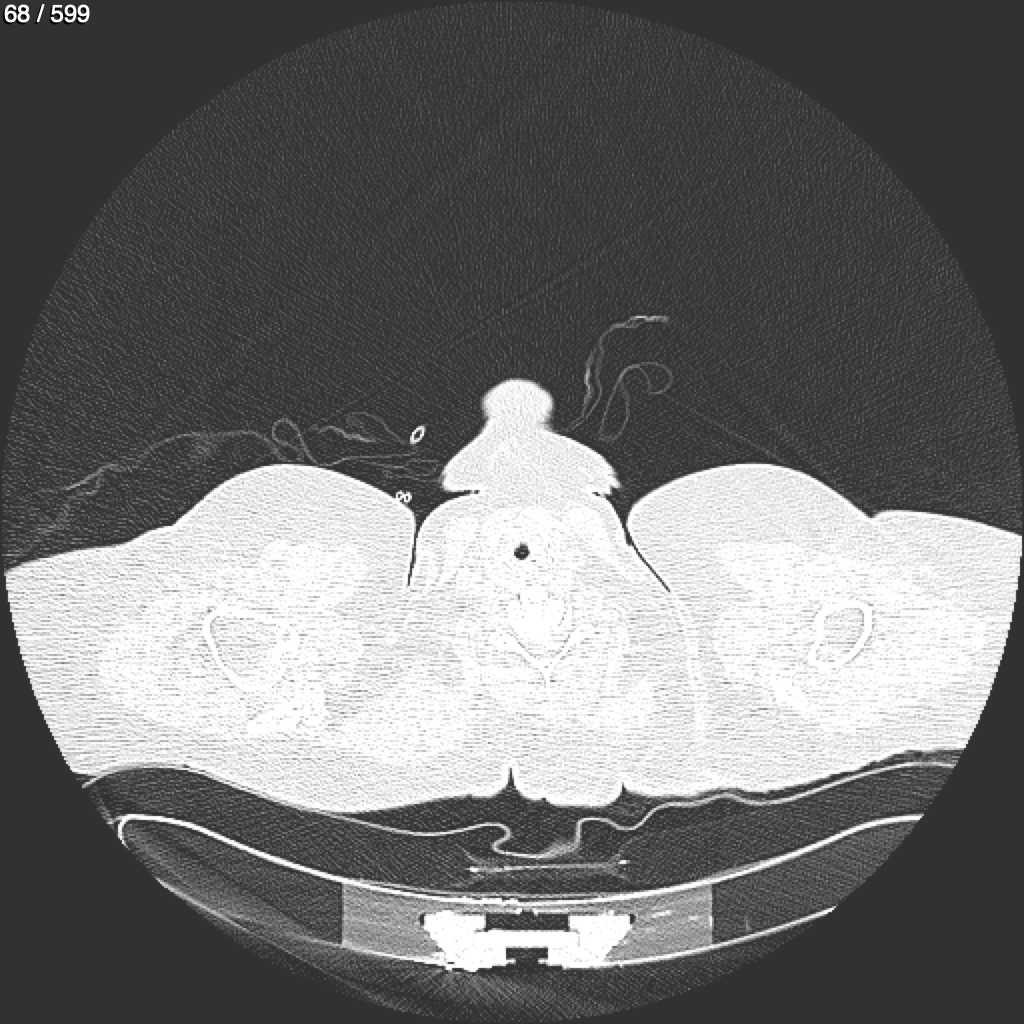

Home G​l​o​r​i​a​ ​G​l​a​d​y​s​ ​B​e​a​s​l​e​y​ ​-​ ​T​ó​r​a​x​ ​T​o​r​a​x​_​S​i​m​p​l​e​ ​(​A​d​u​l​t​o​)